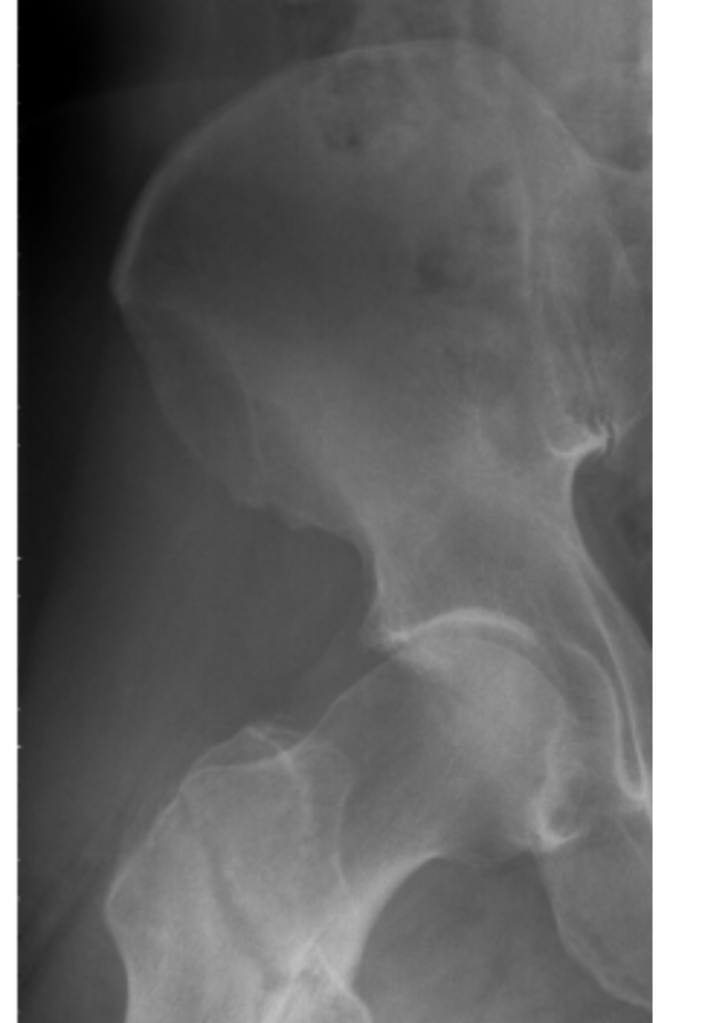

Kay and I recently went back to Methodist Mansfield Hospital, where the paramedics took me after my fall and where I had my surgery and spent 4 days. We picked up the X-rays I had taken in the ER during the predawn hours of Friday, April 26. Aside from a sketch my surgeon drew on the whiteboard of my hospital room to show me the complete break of my femur, I hadn’t seen actual presurgery images.

If you look at the lower left area of the X-ray above, you can clearly see the fracture. In the image below, it’s just right of center. When I finally glimpsed these – even though I knew I’d broken the bone all the way through – it was still surreal to take in. After all, we’re talking about the strongest bone in our bodies, so for me to sustain a total break means I came down on my leg/hip area crazy hard. I’m extremely fortunate I didn’t also break my hip, since the femur fracture was so close to it.

When I saw my surgeon recently, I had another set of X-rays taken that showed the bone is healing great. It takes about 3 months for bone to fully heal, so I probably have almost another month to go.